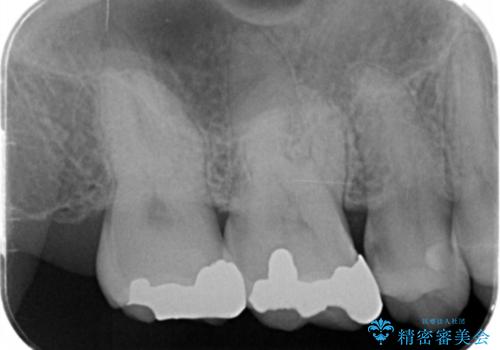

- 口腔内の金属、銀歯を全て除去しセラミックにしたい。と、希望され来院されました。

口腔内の金属を丁寧に除去したのち、精度・審美性に優れるセラミック治療を計画します。

- 20.9万円(ジルコニアクラウン・仮歯・セラミックインレー)費用は治療当時の料金となります